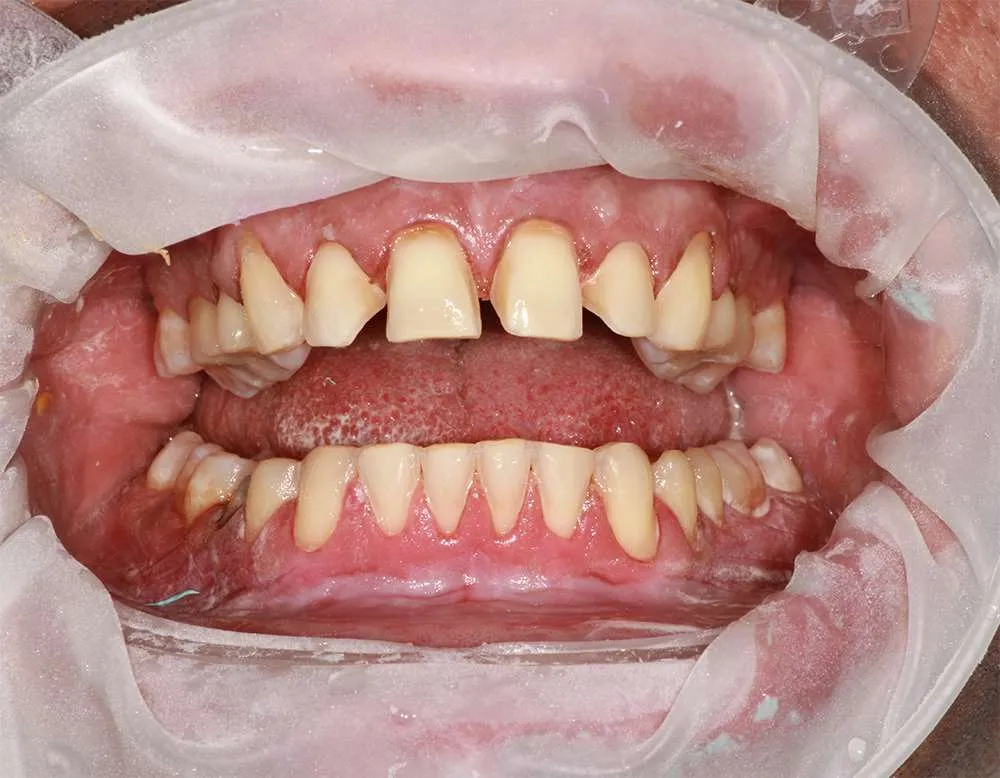

Real Stories, Real Results: Case Studies Showcasing How Our Personalized Approach Transforms Smiles and Lives

Complex Cases

Witness the Remarkable Changes We Can Achieve